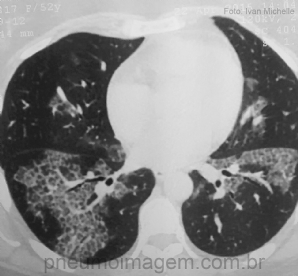

CASO CLÍNICO #27

Abrimos espaço para o caso desse mês para o nosso seguidor do Instagram Ivan Michelle (@IVAN3MICHELLE), que nos enviou essa imagem interessante e pediu a opinião dos nossos amigos. Paciente do sexo feminino, 52 anos. Qual o diagnóstico mais provável? Deixe os ...